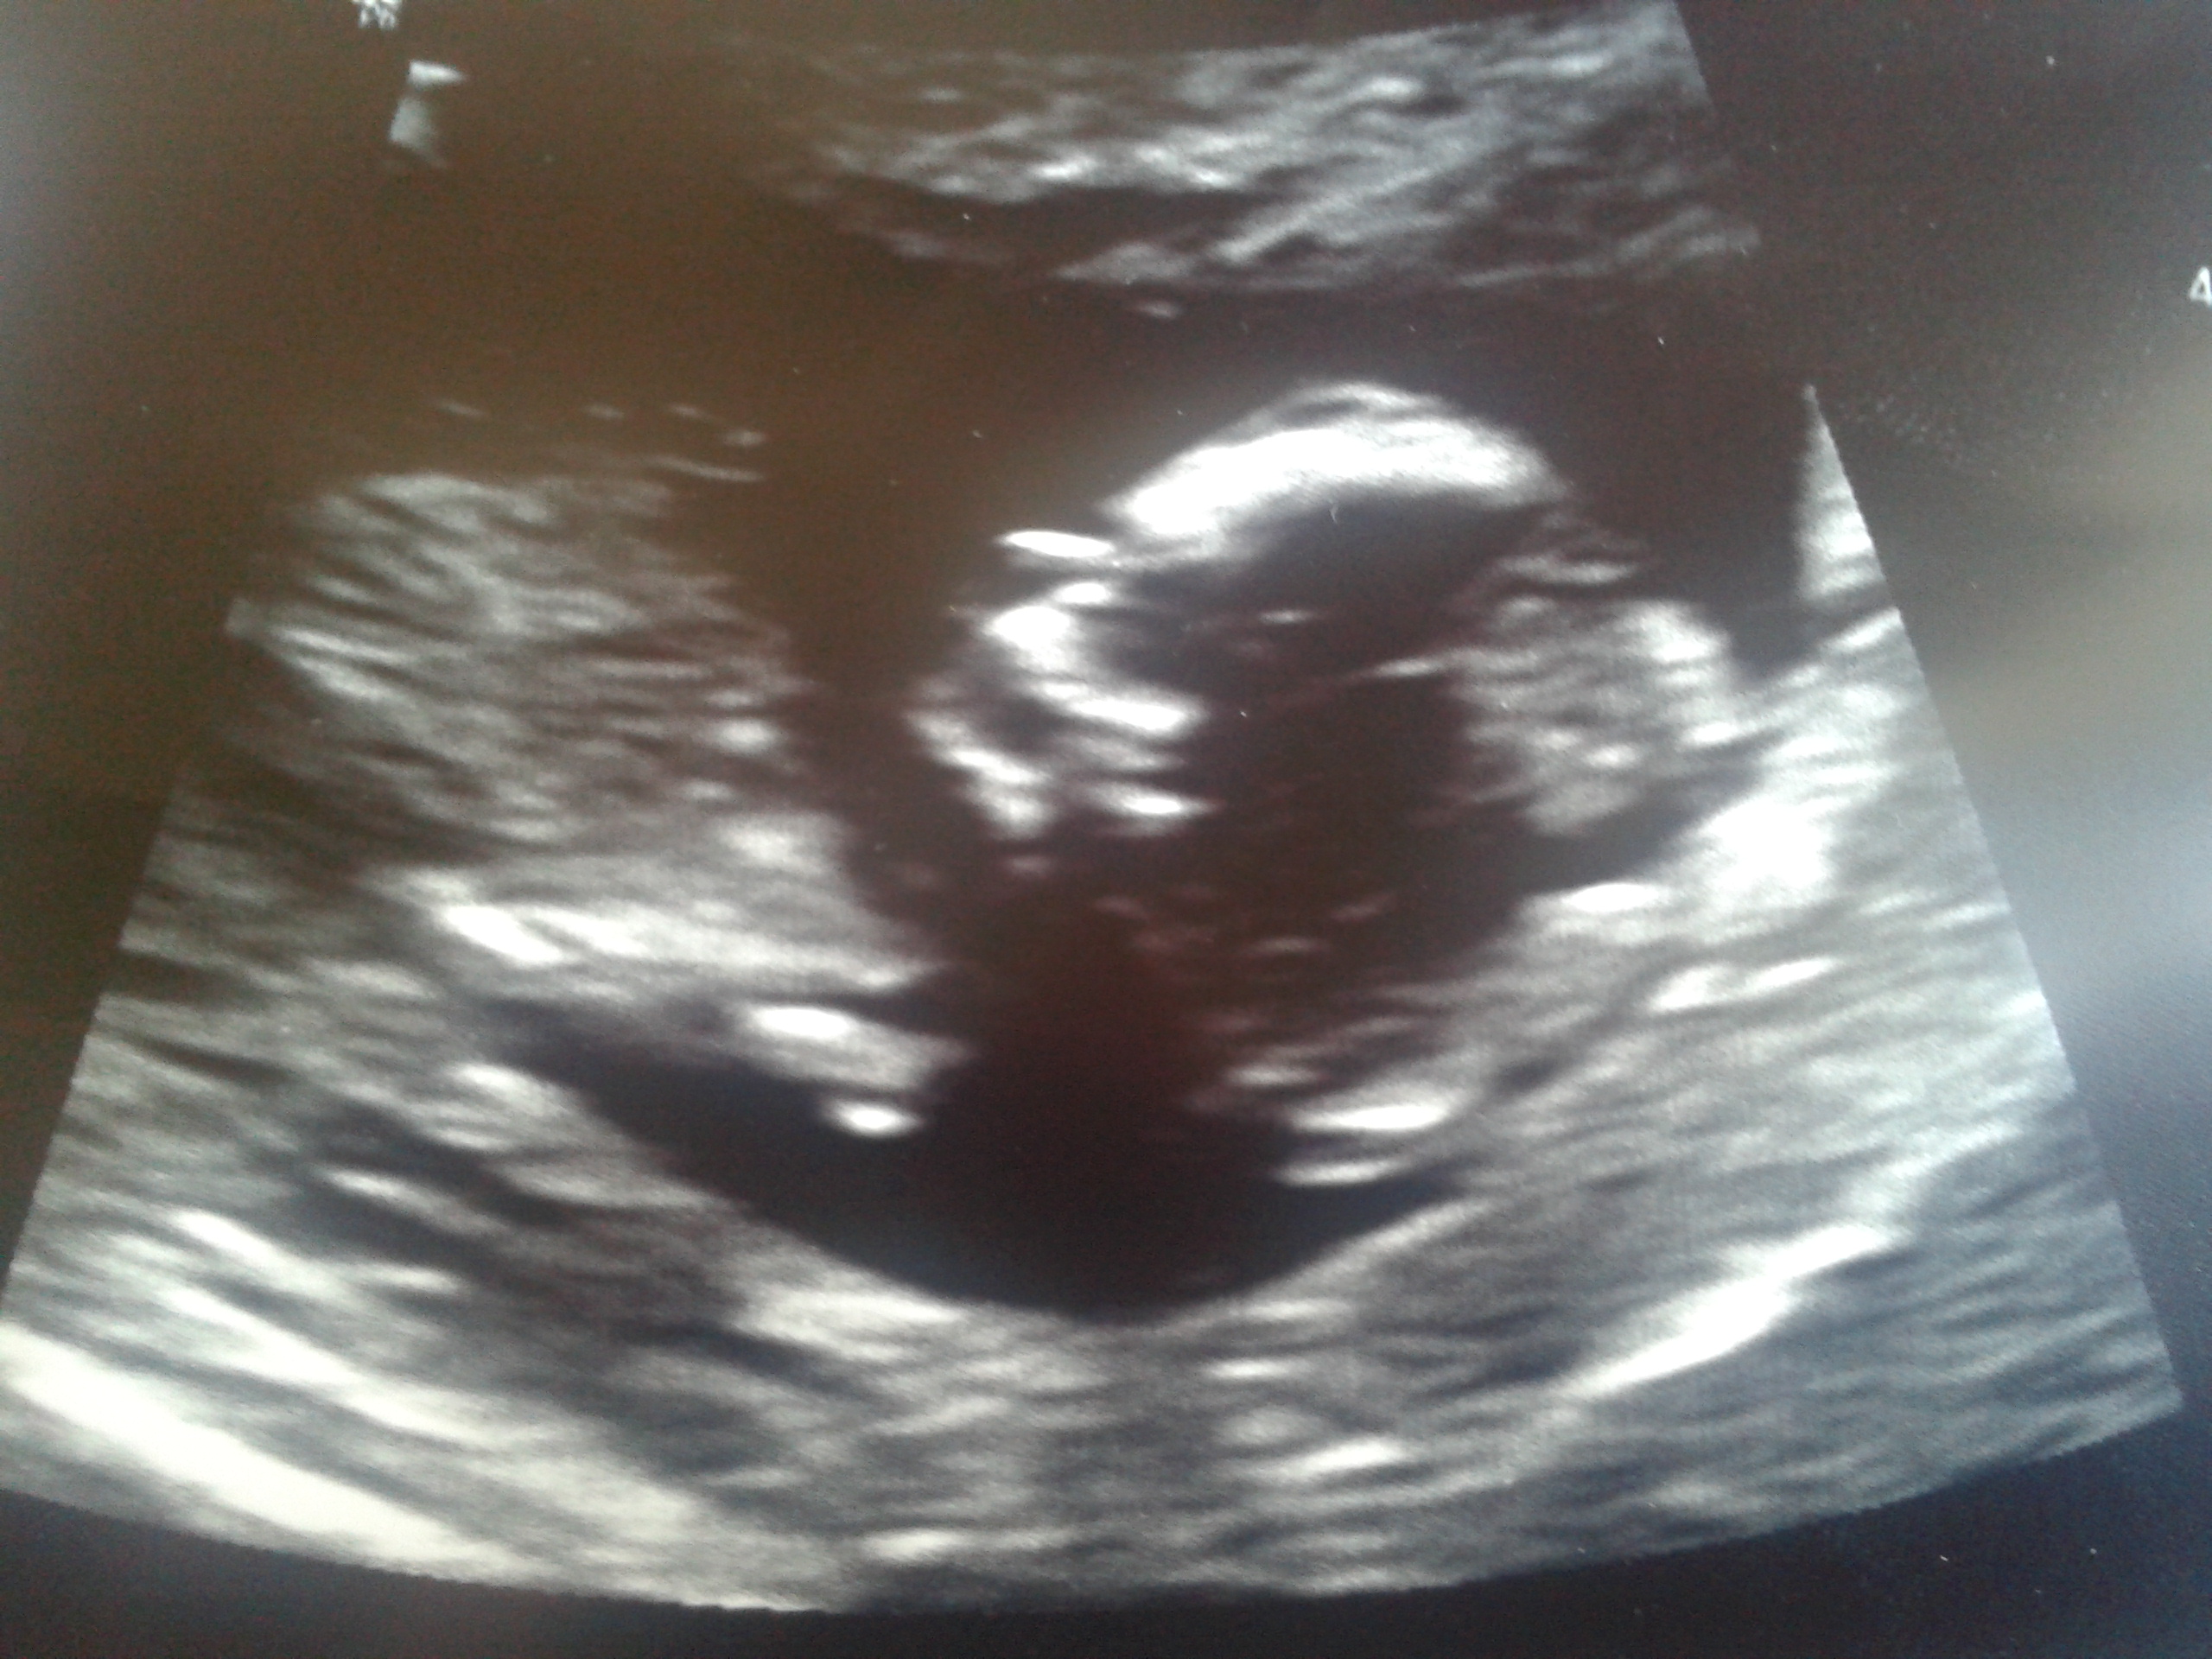

Any guess based on skull theory would be appericiated. DH & I are still deciding we need to find out the gender or need to wait untill birth.

Attachment 3022